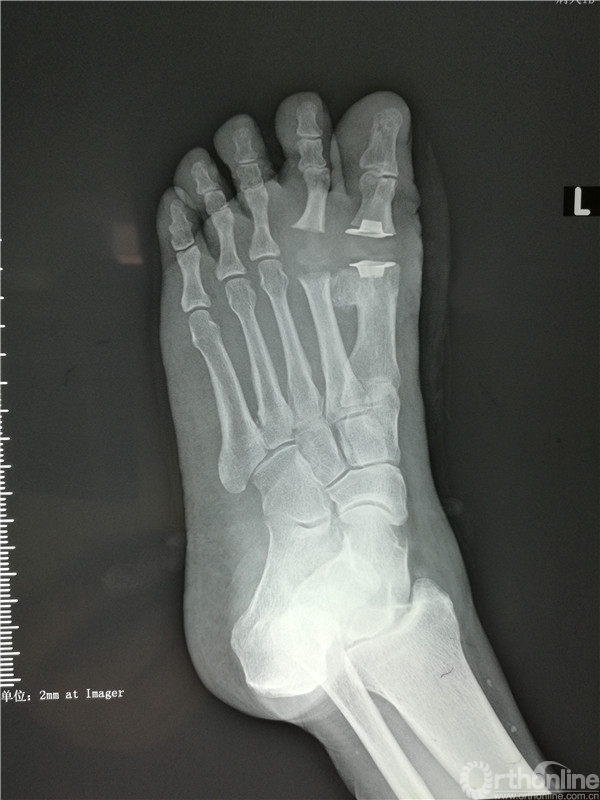

2016年4月7日,烟台市烟台山医院南院骨科收治一例左足跖趾关节骨性关节炎的病人,患者左足严重疼痛10余年,要求治疗的心情迫切。

在张树栋院长及刘克贵主任的支持下,南院骨科组织多次病例讨论,制定了一套对病人有效的治疗方案。以刘克贵主任,孙冰,李宏彦组成的医疗小组。于2016年4月9日上午九时,在腰麻下行左足第1、2 跖趾关节人工关节置换术,患者术后左足的疼痛明显减轻,功能良好,外形美观。